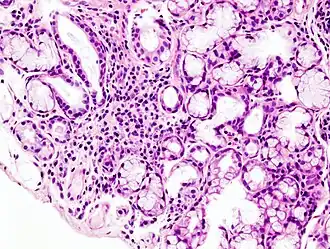

![]() Гистологическая картина локальной лимфоидной инфильтрации малой слюнной железы при синдроме Шёгрена. Биопсия губы. Окраска гематоксилин-эозином | |

- Биопсия малых слюнных желёз. Обнаруживается инфильтрация слюнных желез лимфоцитами.